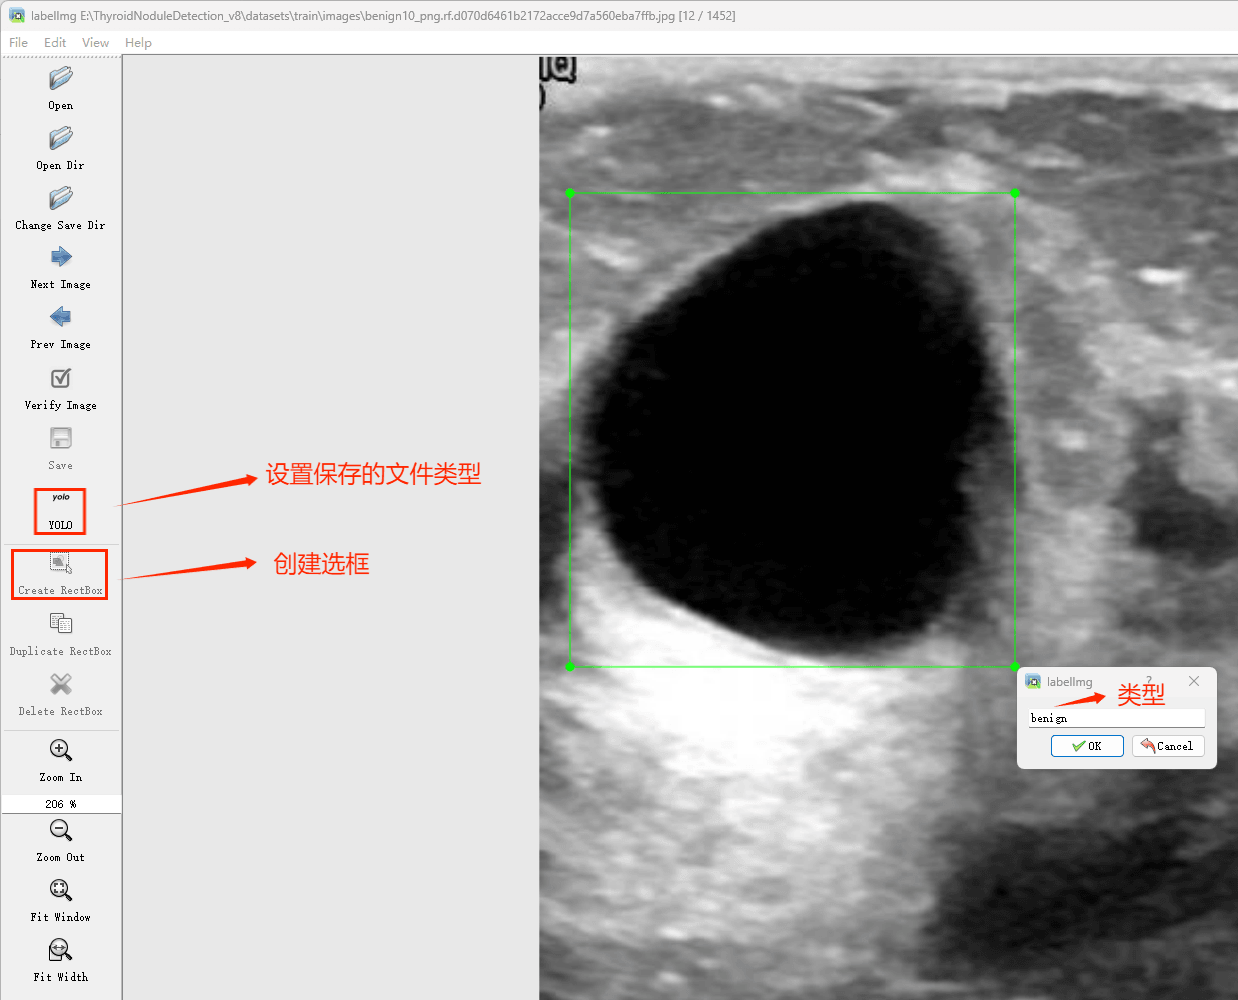

目标检测标注工具

(1)labelimg:开源的图像标注工具,标签可用于分类和目标检测,它是用python写的,并使用Qt作为其图形界面,简单好用(虽然是英文版的)。其注释以 PASCAL VOC格式保存为XML文件,这是ImageNet使用的格式。此外,它还支持 COCO数据集格式。

接下来就开始标注,画框,标记目标的label,然后d切换到下一张继续标注,不断重复重复。